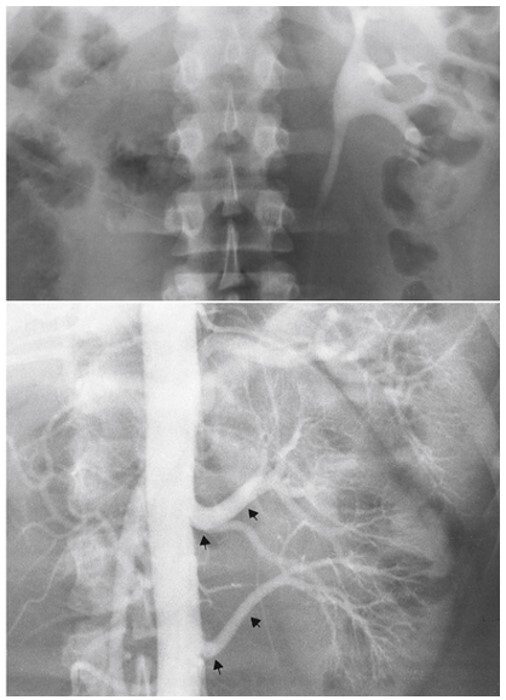

4

Q

What pathology is seen here?

A

Unilateral Renal Agenesis